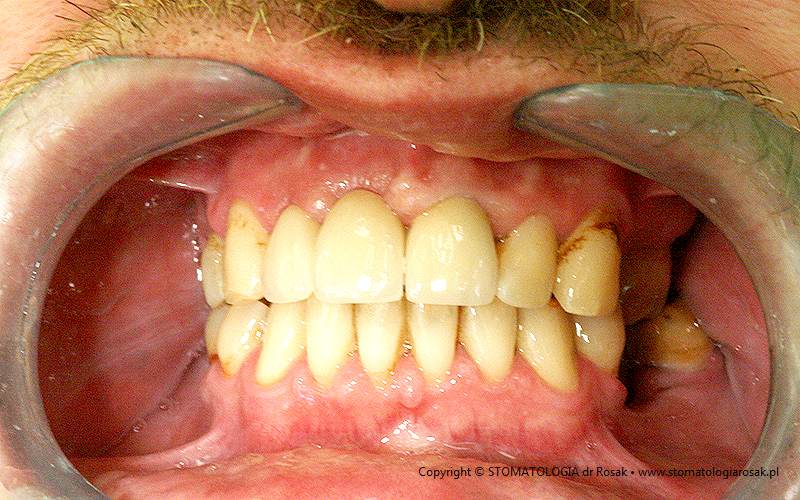

9. Pacjent lat 57- zgłosił się celem usunięcia zniszczonych zębów i wykonania protez ruchomych całkowitych.

NIE USUNĘLIŚMY - ANI JEDNEGO ZĘBA!!!

| 9a. Przed leczeniem |

9b. Gotowe korony i mosty porcelanowe na górze

(trójkę górną prawą pacjent zażyczył sobie nie korygować)

oraz w żuchwie tzw. czapeczki pokrywające oraz zatrzaski kulowe dla lepszego utrzymania protezy ruchomej dolnej |

| 9c. Gotowa praca |